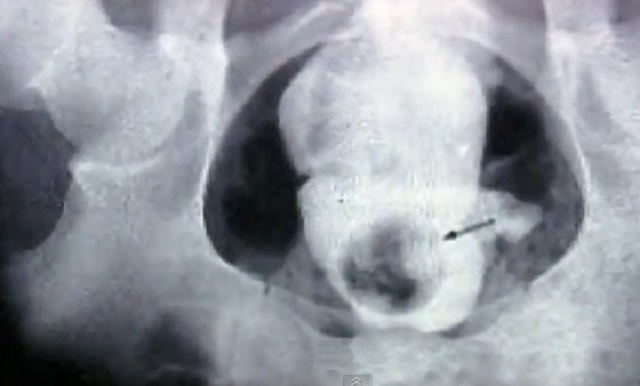

Pe locul 101 se află un accident care a şocat o lume întreagă. Un cuplu de gay a vrut să experimenteze senzaţii tari, la propriu, astfel unul dintre parteneri i-a turnat în rect celuilalt ciment în stare lichidă. Când s-a întărit situaţia a devenit extrem de dureroasă. S-a prezentat de urgenţă la spital, iar medicii au reuşit să-i înlăture greutatea.